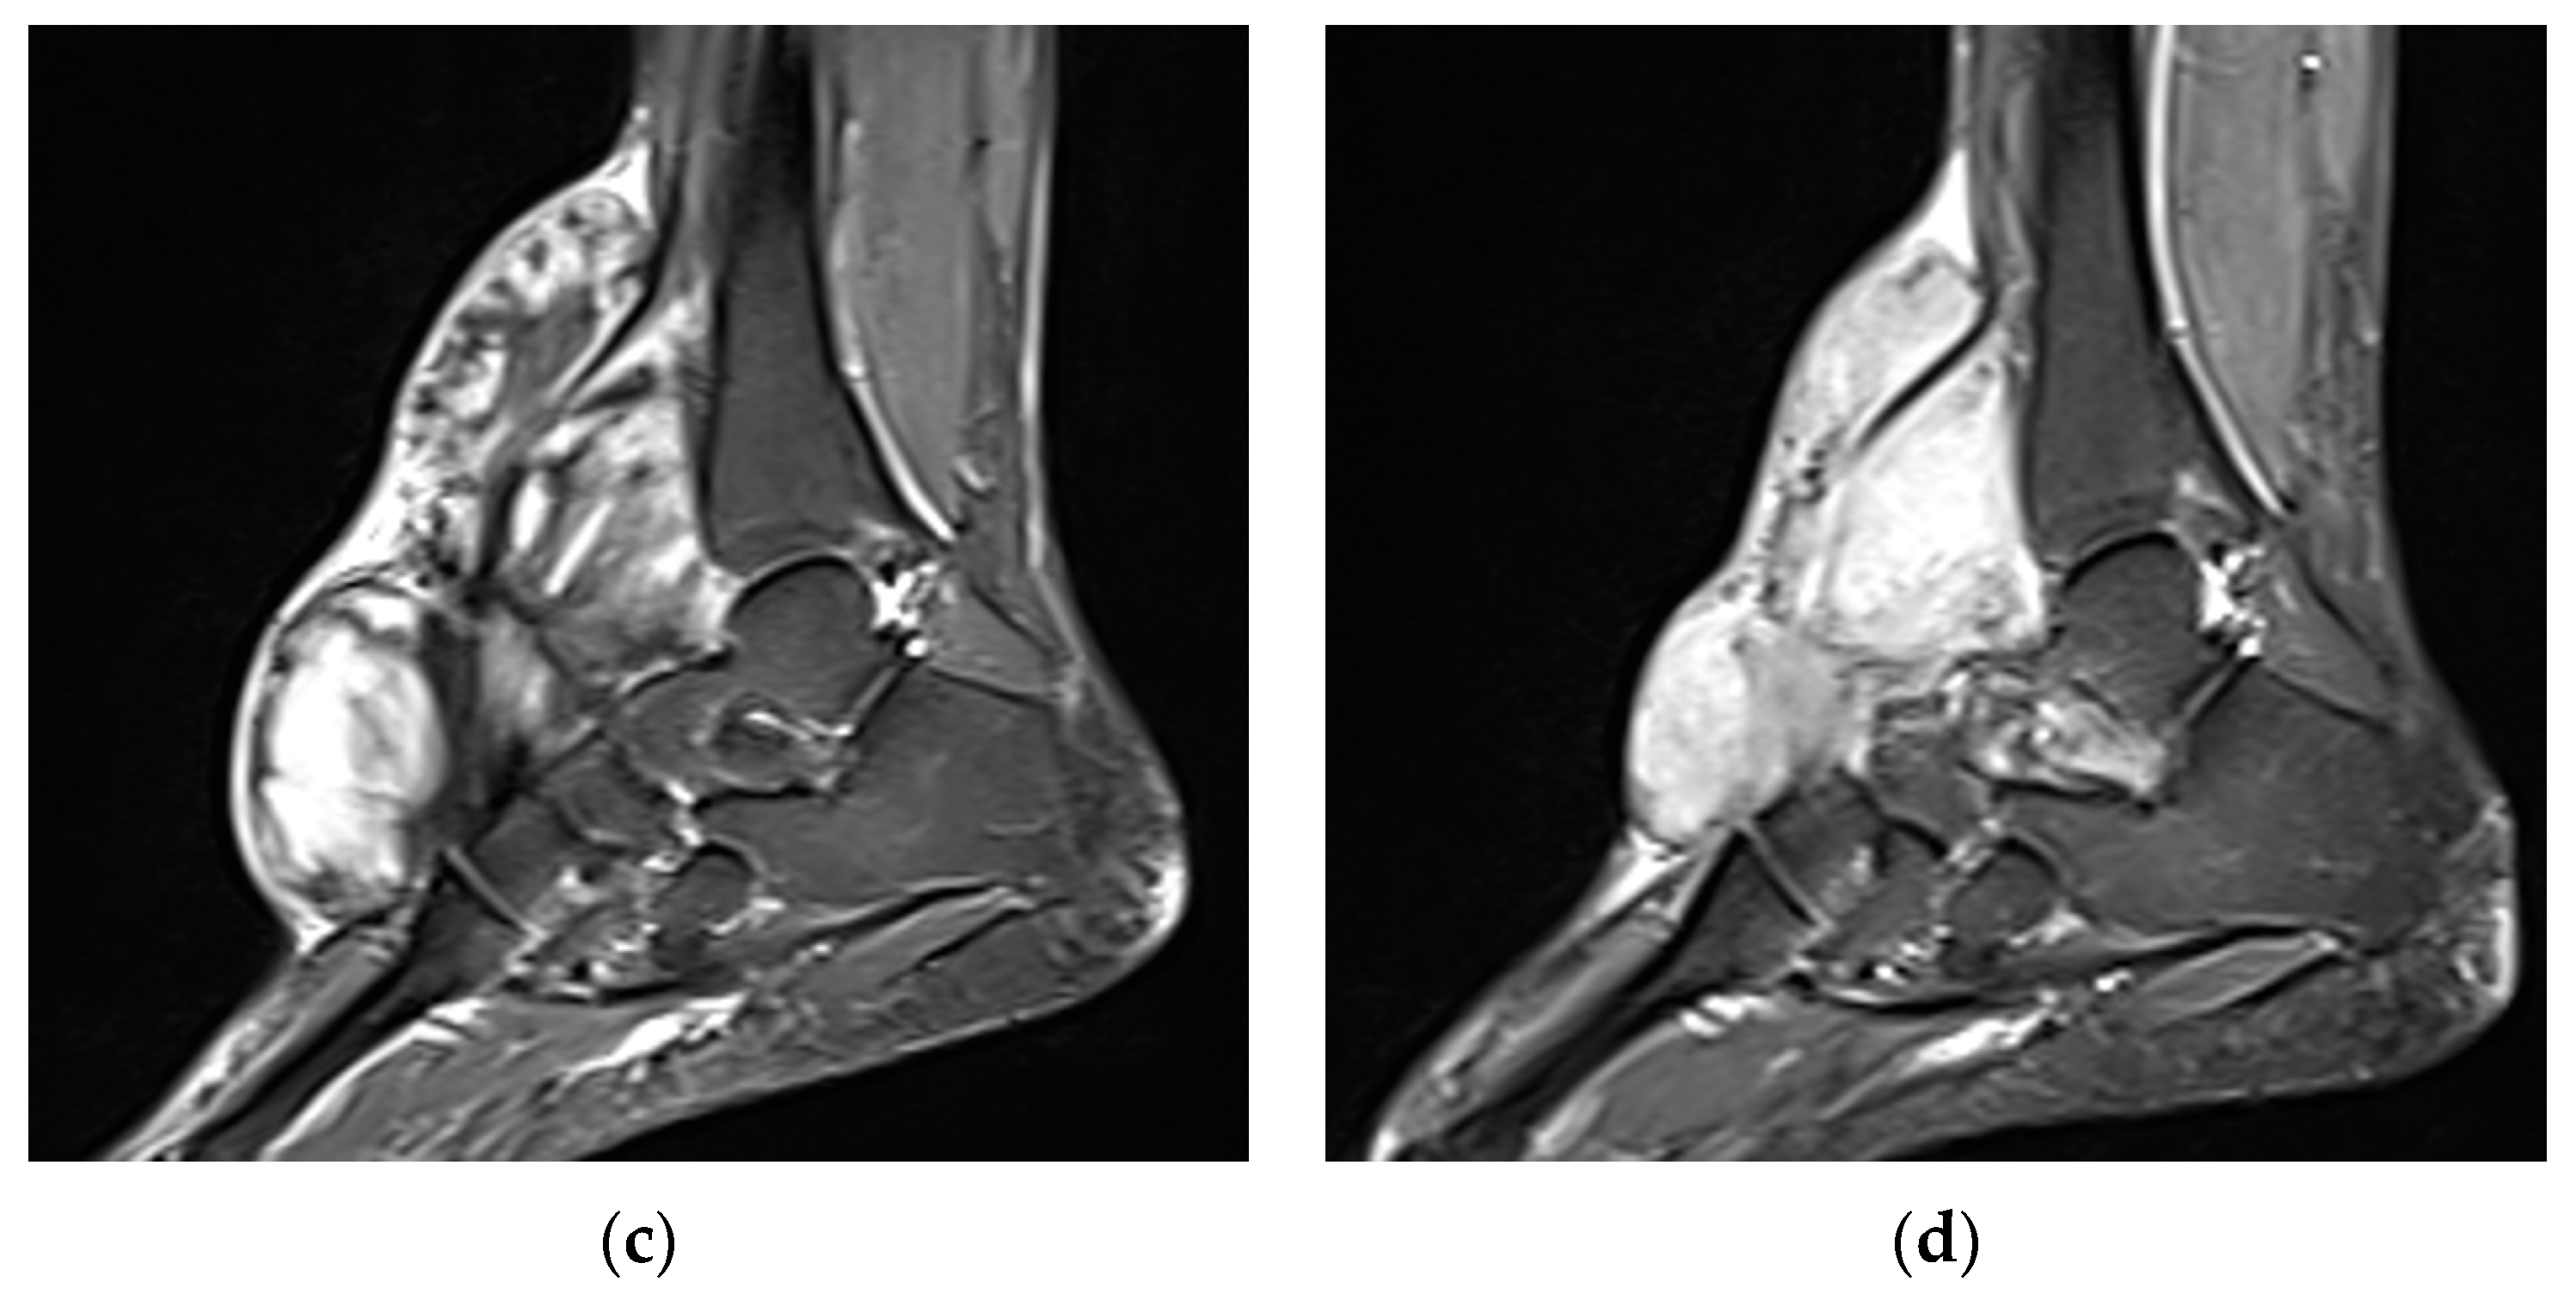

| MRI | Well-circumscribed, heterogenous with nonenhancing T1/T2 hypointense curvilinear areas related to collagen, and T1 intermediate to low/T2 intermediate to high areas related to cellularity or the myxoid matrix. Additional secondary signs (“flame”, “staghorn”, “fascial tail”, etc.) are described in text. |